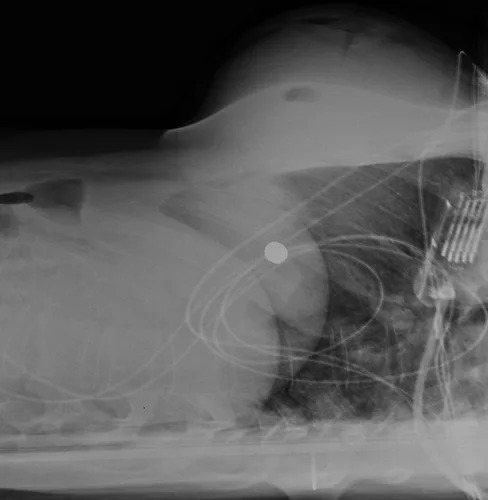

事實證明這位病患的情況真的很特殊,由於她先前有接受隆乳手術,植入了約450毫升的矽膠,所以遇害後子彈從左胸進入,在裡面彈跳之後到了右側,造成右側胸骨骨折,最後停在了右側胸下。大部分從左邊進入的槍傷患者很容易會有生命危險,因為靠近左側有心臟、肺部等重要器官。在這一起個案中,矽膠剛好擋在子彈和器官的中間,達到了保護的作用。

醫生把矽膠拿出來之後也可以清楚地看到子彈擦過的痕跡,這也太驚險了吧QQ 所以隆乳對這起個案上來說,相當於自帶安全氣囊在身上了!